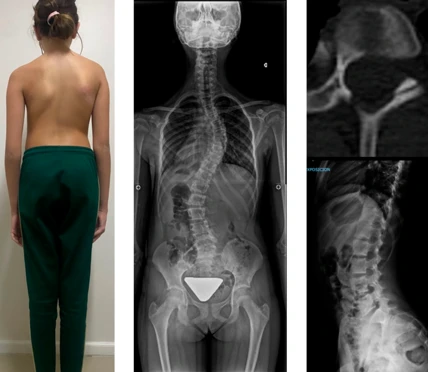

Escoliosis Idiopática

Paciente con escoliosis que presentaba una deformación evidente en la postura. Se decidió la intervención quirúrgica para corregir la curvatura de la columna y mejorar la calidad de vida.